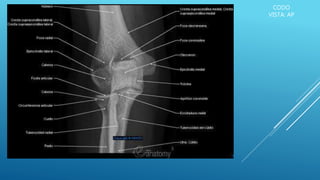

CODO

VISTA: AP